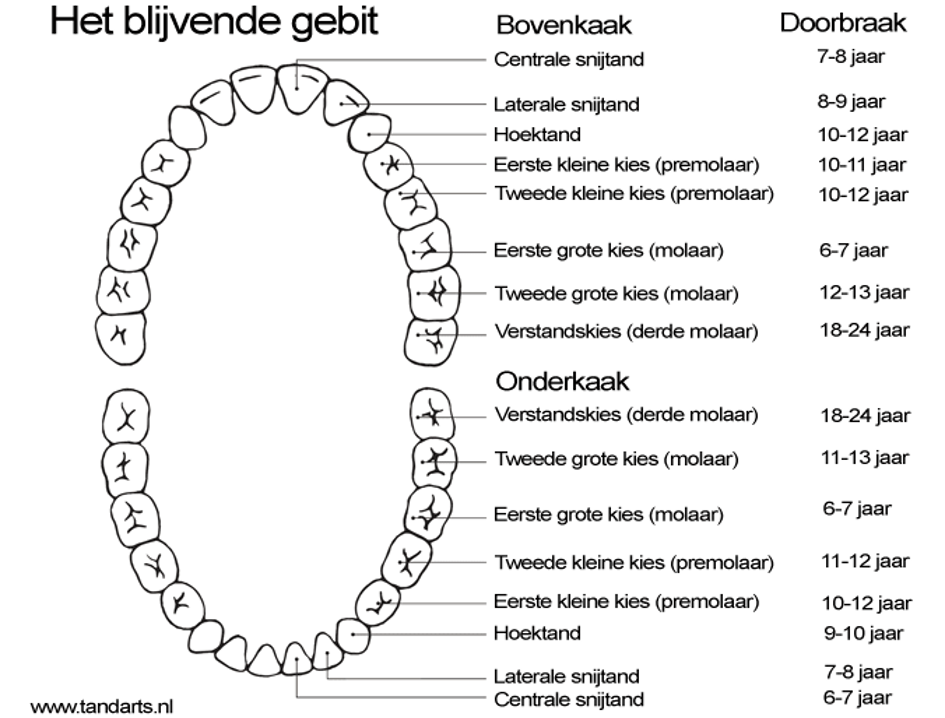

Het (melk)gebit Tandarts.nl

Mensen hebben ruimte voor 32 elementen, bestaande uit tanden en kiezen. De verstandskiezen zijn de laatste kiezen die achter in de mond naar boven komen. Normaal gesproken gebeurt dit tussen het 18de en 22ste levensjaar. Tegenwoordig hebben veel mensen te smalle kaken voor alle 32 elementen en passen er maar 28 tanden en kiezen in de kaak (of.

Op welke leeftijd komen de tanden door? Lees het hier!

Rond de leeftijd van 5 à 6 jaar beginnen de verstandskiezen in het tandvlees te vormen. Echter is dit op een orthopantomogram (röntgenfoto van de kaak) niet altijd zichtbaar. Meestal kunnen ze pas op de leeftijd van 10 à 11 jaar met een röntgenfoto worden gelokaliseerd. Het proces van doorkomende verstandskiezen verschilt van persoon tot.

Mensen hebben in de mond ruimte voor 32 tanden en kiezen. De verstandskiezen zijn de laatste kiezen die achterin de mond naar boven komen. Normaal gesproken gebeurt dit tussen het 17e en 22e levensjaar. Dit valt gelijk met het moment dat pubers volwassen worden en met het stijgen van de leeftijd zou ook het verstand moeten komen. Vandaar de naam.